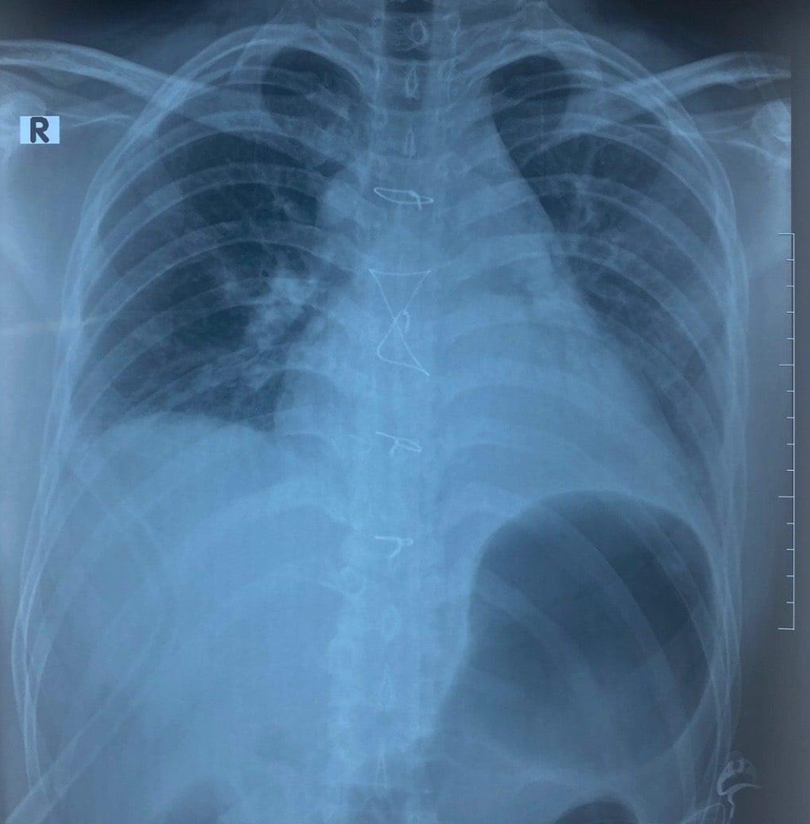

| Ảnh chụp X-quang của bệnh nhân (Ảnh: BVCC) |

Bệnh nhân vào Bệnh viện Trung ương Quân đội 108 trong tình trạng khó thở với một vết bầm tím nhỏ ở ngực, kèm theo tiếng tim nghe hơi mờ. Siêu âm tim, các bác sĩ phát hiện bệnh nhân có dịch trong khoang màng tim. Chụp CT thấy bệnh nhân bị vỡ xương ức, gãy cung trước xương sườn 7,8 bên phải, tràn dịch khoang màng tim và màng phổi phải, vỡ gan độ 3.